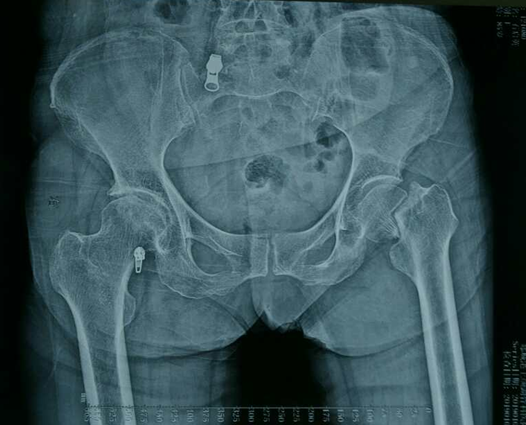

术后片

很快,蒋守海闫成尚手术小组为老人施行了左侧人工股骨头置换术。术中,手术小组尽量减少手术创伤,减少术中出血,缩短手术时间,1小时后顺利完成手术。